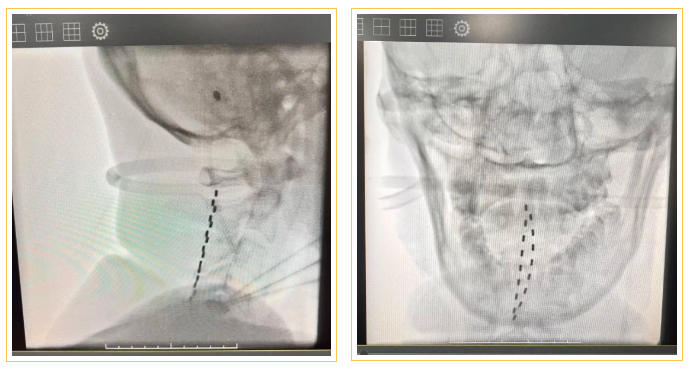

近日,河池市中医医院颅脑外科成功完成河池市首例脊髓神经电刺激电极植入术(SCS),为神经功能障碍患者的康复治疗带来新希望!

脊髓电刺激植入术是脑机接口技术在临床领域的重要应用。手术在数字减影血管造影(DSA)引导下进行,通过精准植入电极,根据患者个体情况对特定脊髓节段进行持续的电刺激,以调节异常神经通路,具有微创、可逆、可调控等特点,实现精准化治疗。临床上,SCS为肢体痉挛、肌张力障碍、偏瘫、慢性疼痛及意识障碍等神经系统难治性疾病提供了新的治疗选择,尤其为长期昏迷等慢性意识障碍患者带来了促醒康复的新希望。